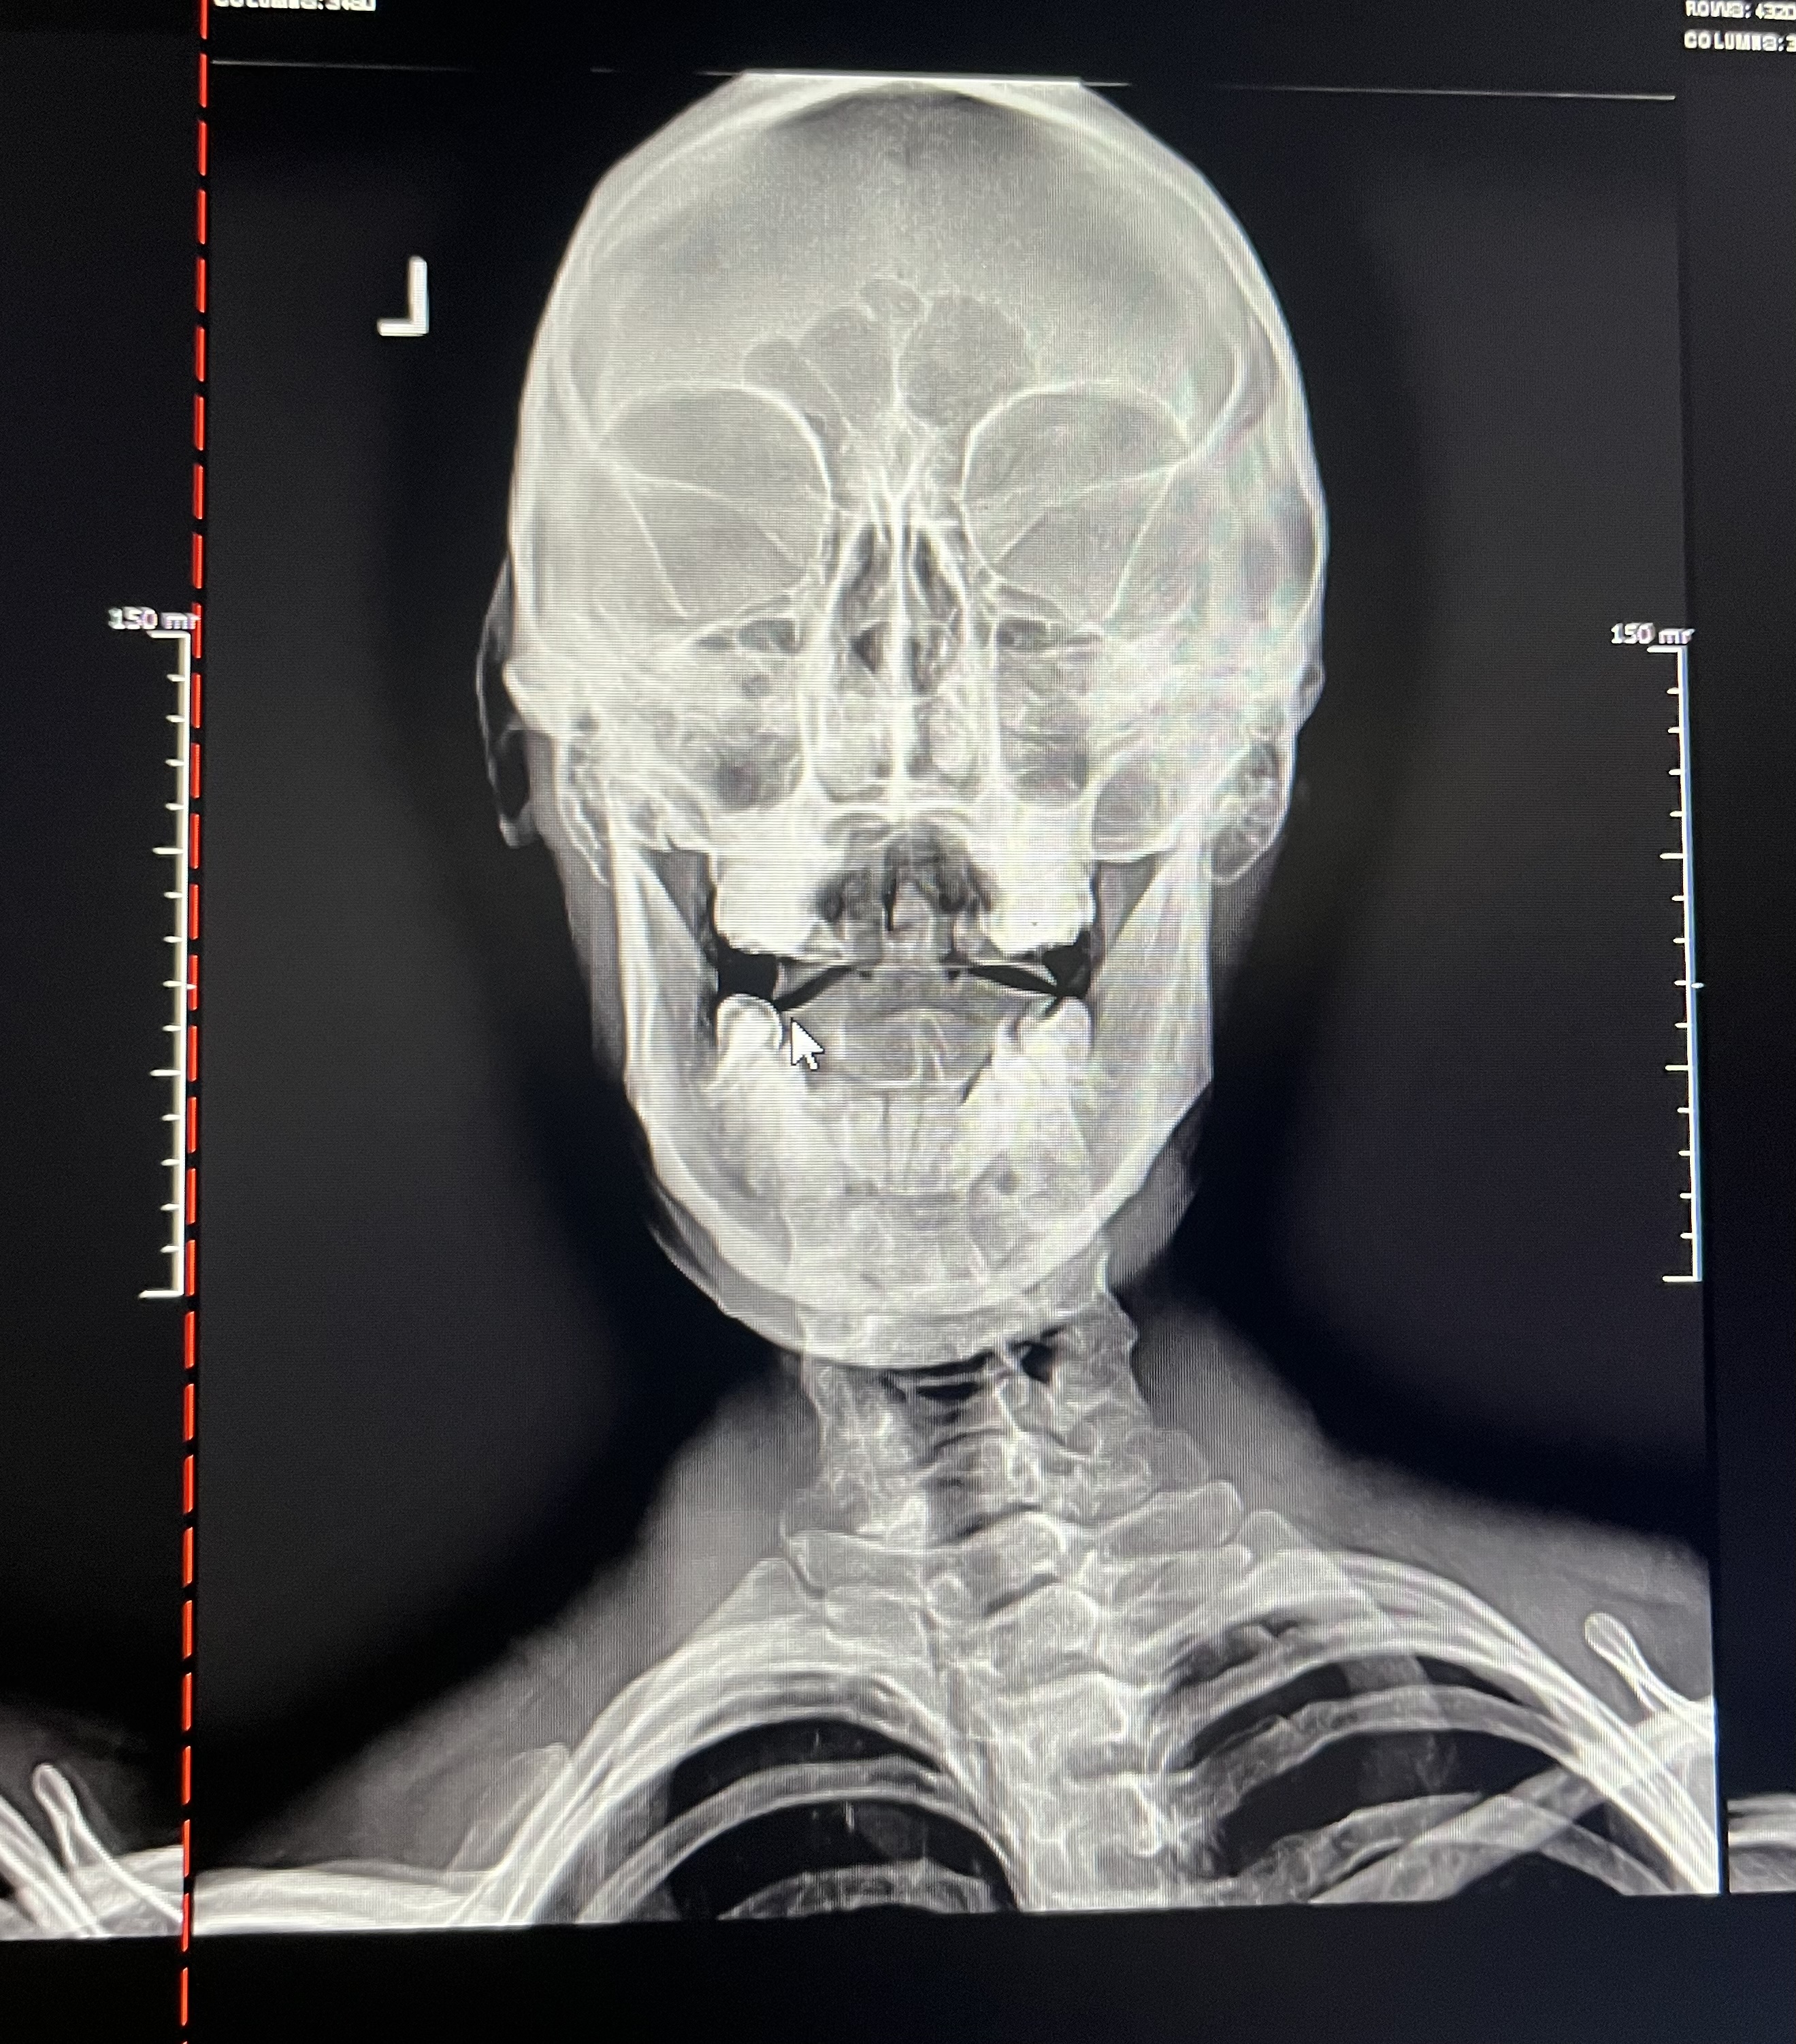

Following a series of neurologic scans, we take x-rays. These x-rays are also different. We take images with the head tilted to the left and also to the right so that we can assess the incorrect motion of the first and second bone of the neck.

This is how we determine the source of the dysfunction. From there, we adjust just that one bone, just that one side as minimally as possible and let the body do the rest.